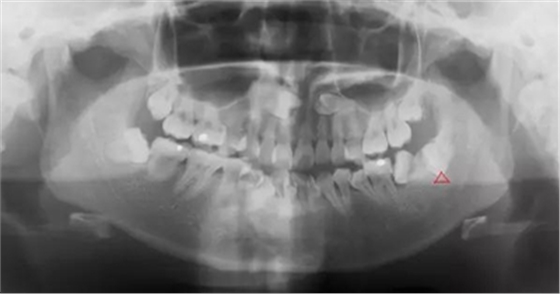

4.對頜牙缺失,智齒伸長